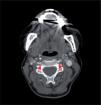

Figura 1.

Origem da artéria vertebral esquerda do arco aórtico (seta).